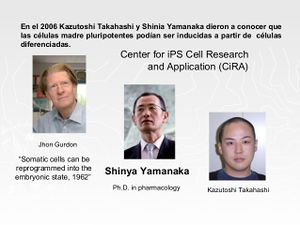

Mediante una serie de experimentos desarrollados a partir de 2007, se ha podido demostrar que incluso las células somáticas ya diferenciadas pueden ser reprogramadas genéticamente, obteniendo a partir de ellas un linaje de células en un estado embrionario.

De este modo, los investigadores japoneses Kazutoshi Takahashi y Shinya Yamanaka, del Departamento de Células Madre de la Universidad de Kyoto[5], demostraron satisfactoriamente la posibilidad de inducir la producción de células madre pluripotentes (células iPS) a partir de fibroblastos embrionarios o de adulto de ratón.[4]

Dicha tecnología es muy prometedora que demuestra que la obtención de células proliferativas útiles para aplicaciones médicas tiene una vía de exploración a través de la llamada «reprogramación celular» o «reprogramación genética». Esta metodología podría aplicarse a partir de células de un tejido no dañado de un paciente al que se desea curar una enfermedad degenerativa que afectase a otro tejido, haciendo innecesaria la producción de embriones por trasplante nuclear.